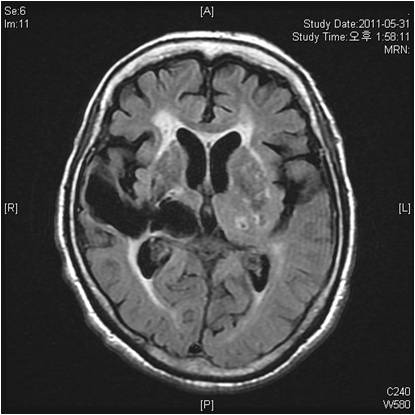

뇌경색 예방법

뇌경색 을 예방하기 위해서는 위험요인의 관리가 제일 중요하고요. 대표적인 위험 요인으로는 고혈압, 당뇨, 심장질환, 고지혈증, 비만 등이 있으며 그 말고도 수면 무호흡증이나 운동부족, 과음 등이 이에 해당하고요. 이런 위험인자를 지닌 사람은 뇌경색과 같은 뇌졸중 발생 위험이 그 이상으로 더 많으므로한다고 합니다. 콜레스테롤을 줄이는 건강식단, 꾸준한 운동, 금연, 금주, 혈압관리, 혈당관리 등을 하여 위험인자를 낮추는 것이 좋습니다.